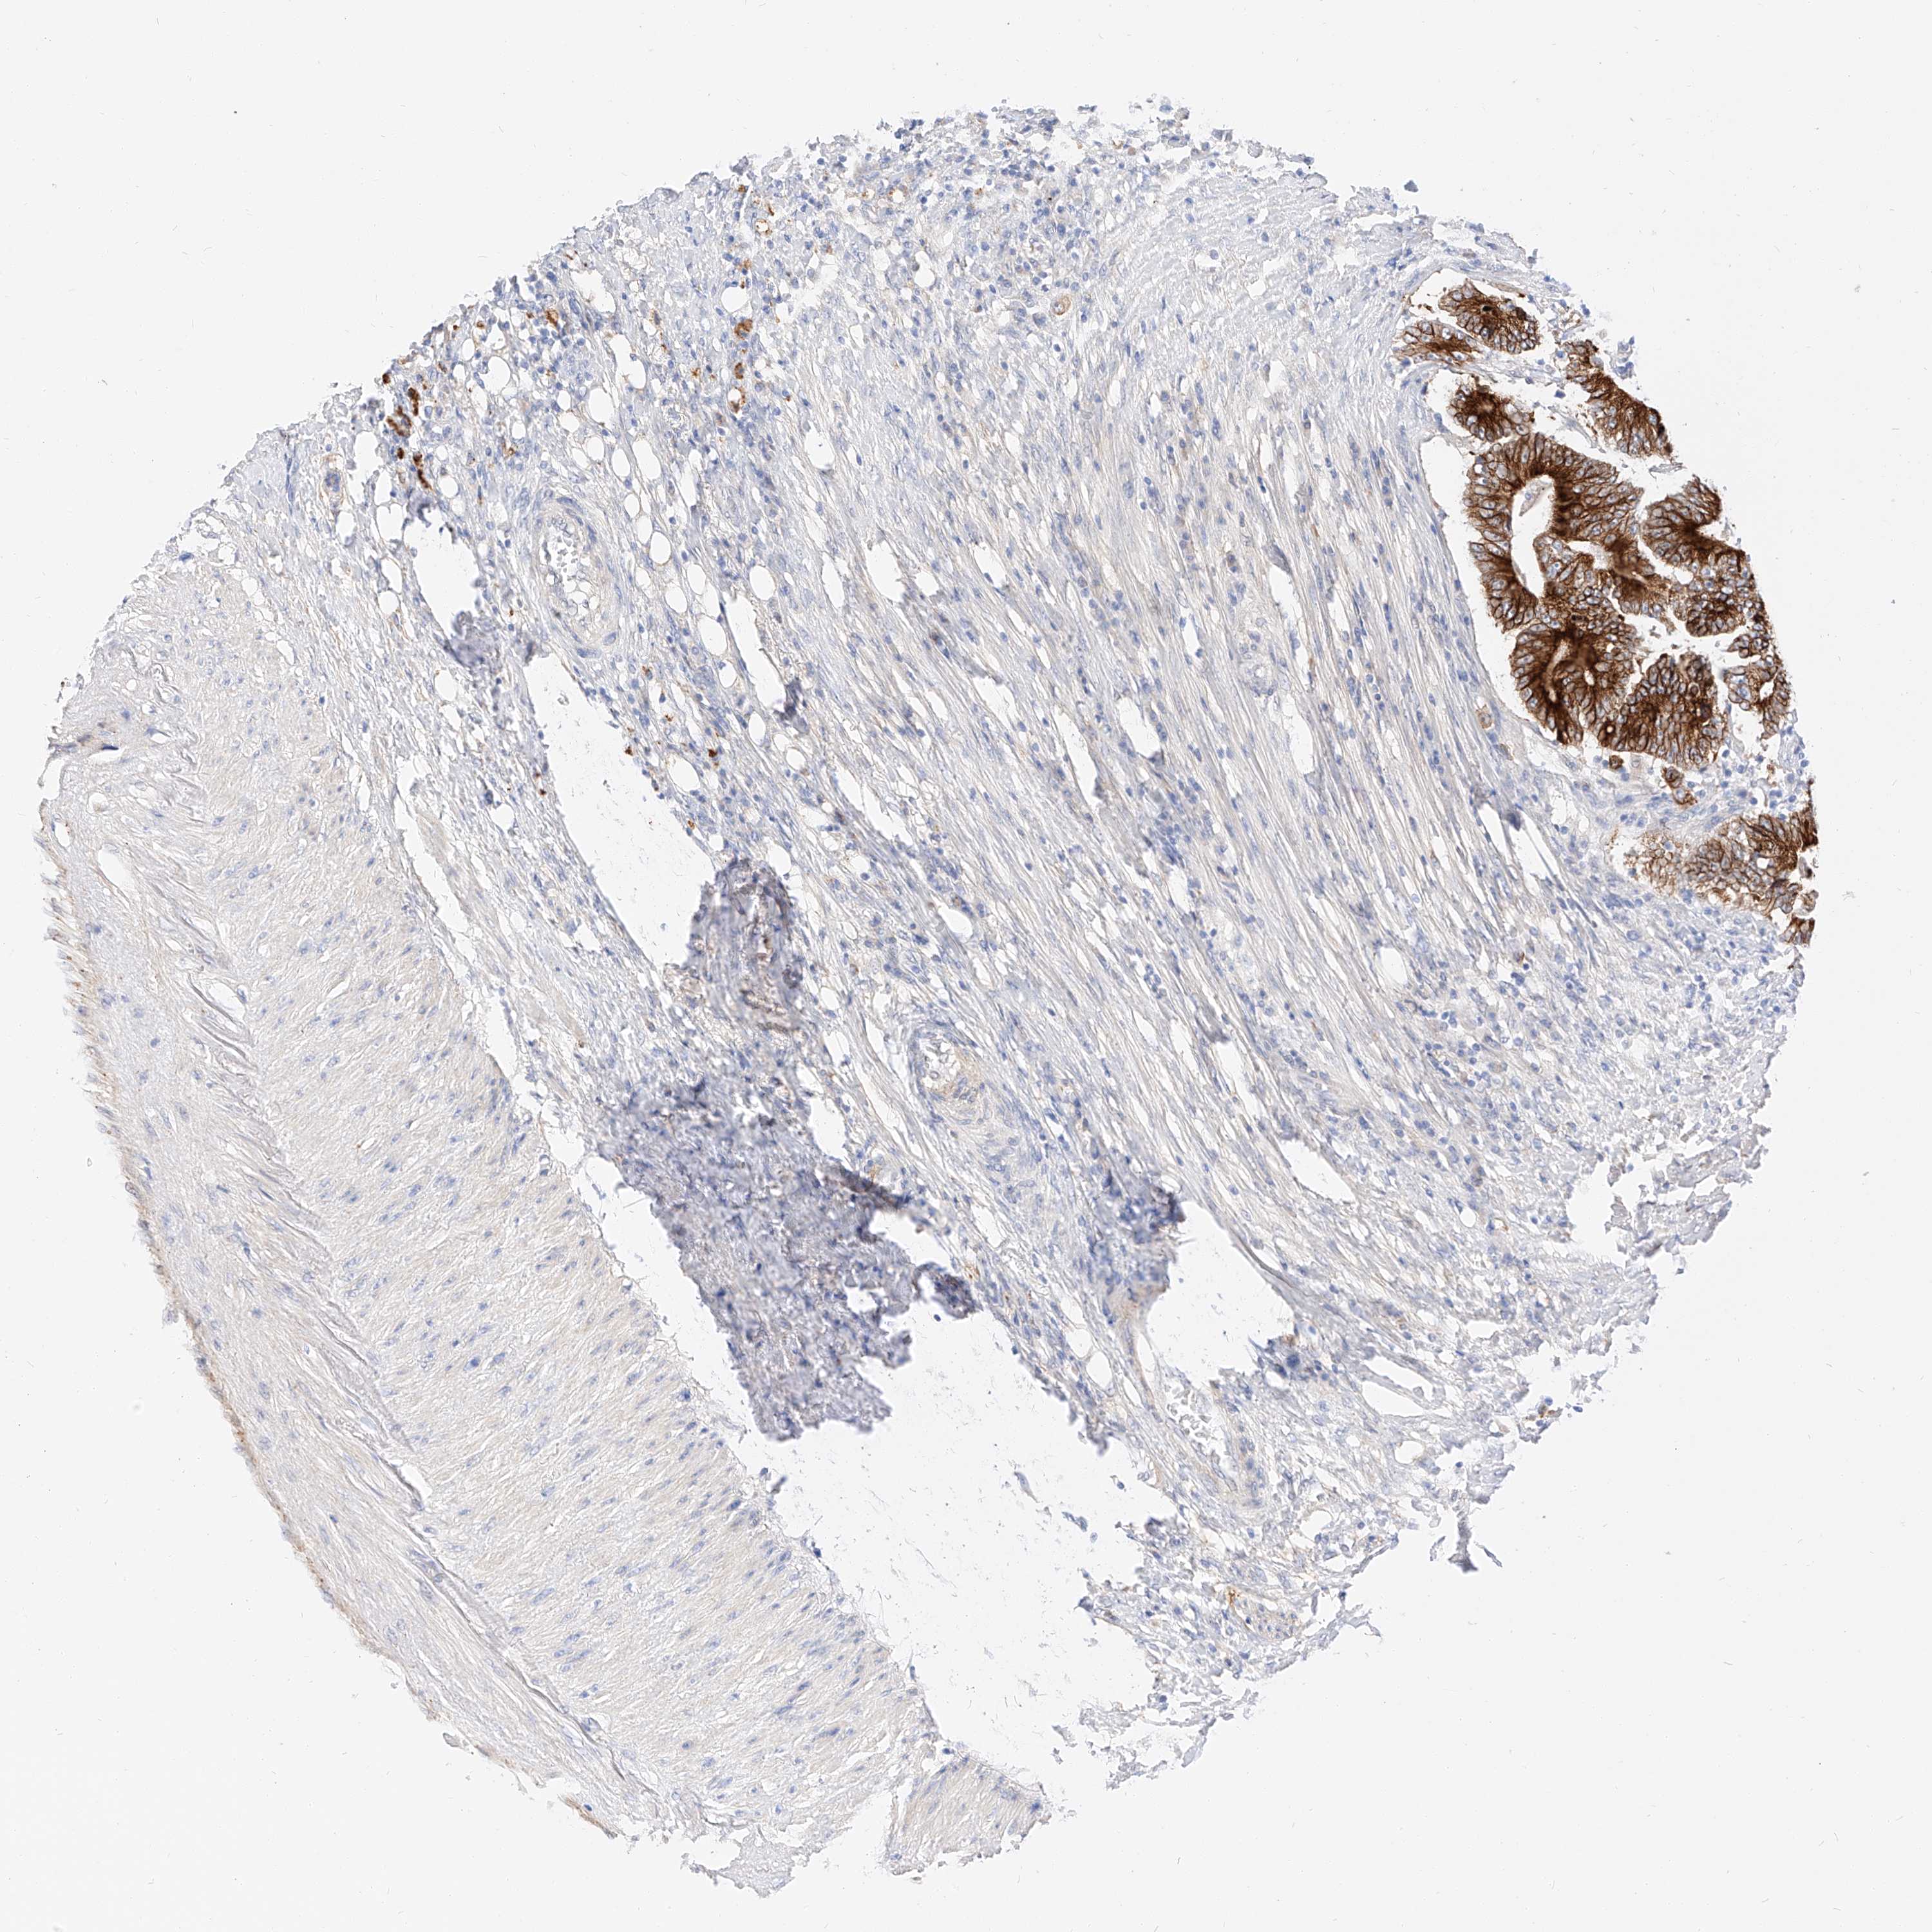

CANCER COLORECTAL CANCER Show tissue menu

Colorectal cancer

Human cancer

Colon adenocarcinoma